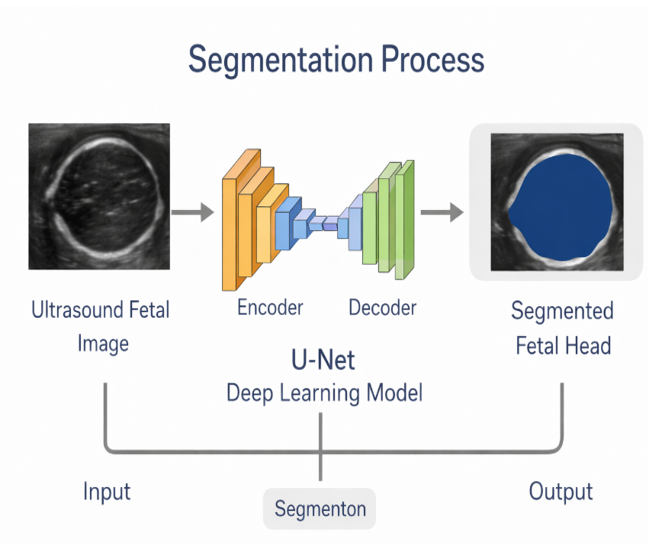

SEGMENTATION

• Segmentation is used to automatically extract the fetal head region from the ultrasound image.

• A U-Net deep learning model is used because it is well-suited for medical image segmentation.

• The encoder extracts important features and edges, while the decoder reconstructs the head boundary to produce a segmentation mask.

• This mask removes background regions and isolates the fetal head with accurate contour detection.

• The segmented head region is then used for computing BPD, OFD, HC and Cephalic Index with improved reliability.

Purpose of Segmentation

✓ Reduces operator dependency

✓ Eliminates manual tracing errors